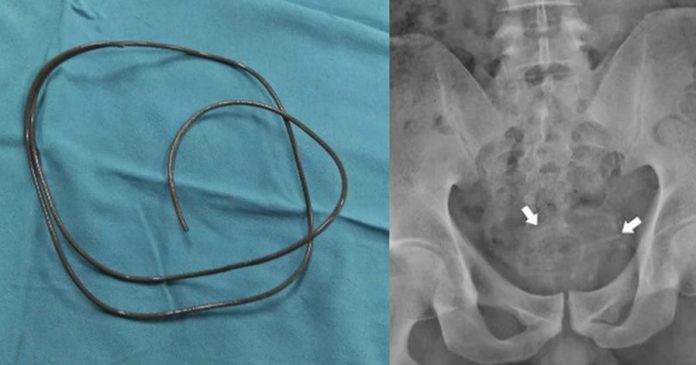

医师为男子照X光后发现,男子的膀胱内的确卡着一个异物,呈现线状缠绕。医师也指出,幸好这条耳机线没有碰触到膀胱壁,否则可能会导致膀胱上出现多个孔,必须进行更多手术来修复。医师最后用镊子慢慢地把这条耳机线拉出来,医师指出,这条耳机线长约80公分,宽约3厘米。